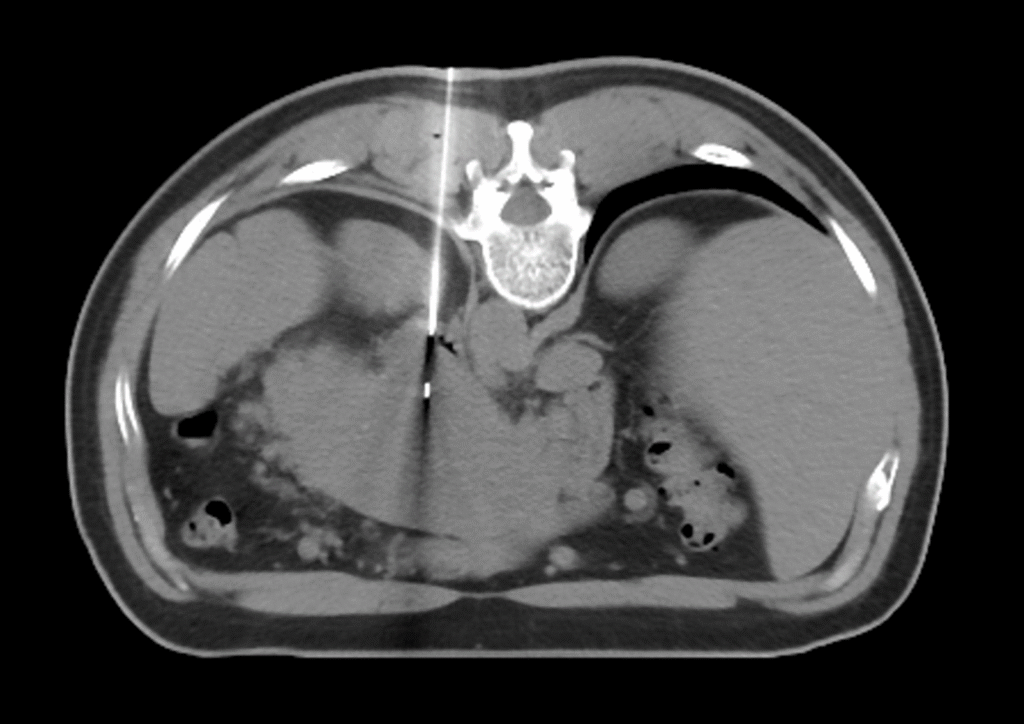

Needle Biopsy (Image guided)

A needle biopsy is a common, minimally invasive procedure used to obtain a small sample of tissue (from a lump or abnormal area) for examination under a microscope. This is often necessary to determine the exact cause of an abnormality seen on an imaging test.

A needle biopsy is an image-guided procedure. This means the doctor uses real-time imaging technology to see inside your body, pinpoint the exact location of the abnormal tissue, and guide the needle safely to the target.

| Computed Tomography (CT) Scan | Used for deeper lesions, such as those in the lung, abdomen, bone, or other areas not clearly seen on ultrasound. It provides a detailed, cross-sectional view. |